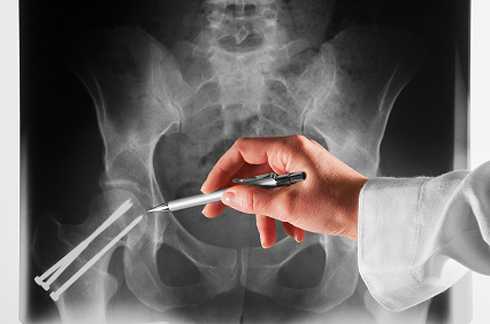

Для диагностирования ортопедических заболеваний необходимо обращаться к специалисту – ортопеду. Основные методы диагностики в ортопедии, это общий осмотр пациента, пальпация областей, где локализуется боль, собирание данных о заболевании путем опроса пациента, и рентгенография, на которой всегда можно увидеть внутренние ортопедические деформации или изменения опорно-двигательного аппарата пациента.

Диагностика предусматривает осмотр, пальпацию, подробный опрос, рентгенографию.